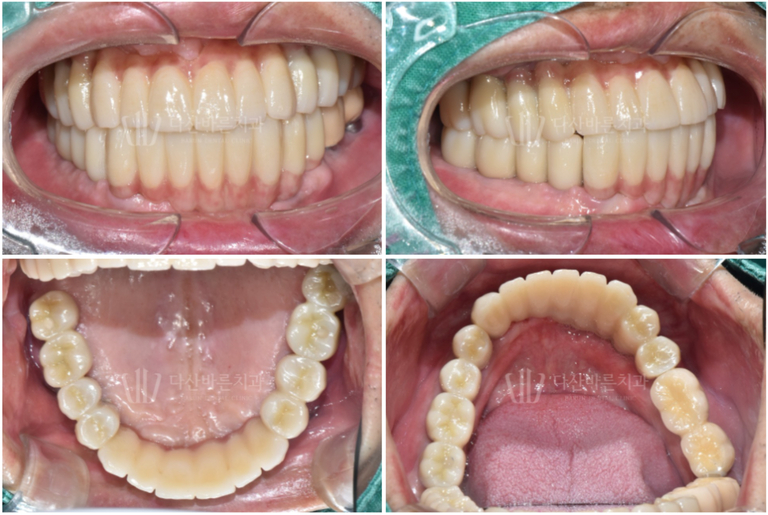

Ảnh bên dưới là ảnh chụp hoàn chỉnh bằng miệng.

Vì tính thẩm mỹ là khía cạnh quan trọng nhất của răng cửa nên

chúng tôi đã thêm vật liệu sứ màu hồng vào

những vùng nướu có vẻ hơi thụt vào để tạo vẻ tự nhiên.

(Trong phim X-quang bên trên, ngay cả vùng nướu cũng có màu trắng,

khiến răng trông dài hơn, nhưng thực tế thì bạn có thể thấy tính thẩm mỹ đã được cải thiện đáng kể. ^^)

Chúng tôi rất vui mừng vì quá trình điều trị đã kết thúc thành công và

bệnh nhân đã lấy lại được cảm giác ăn nhai khỏe mạnh như trước ^^